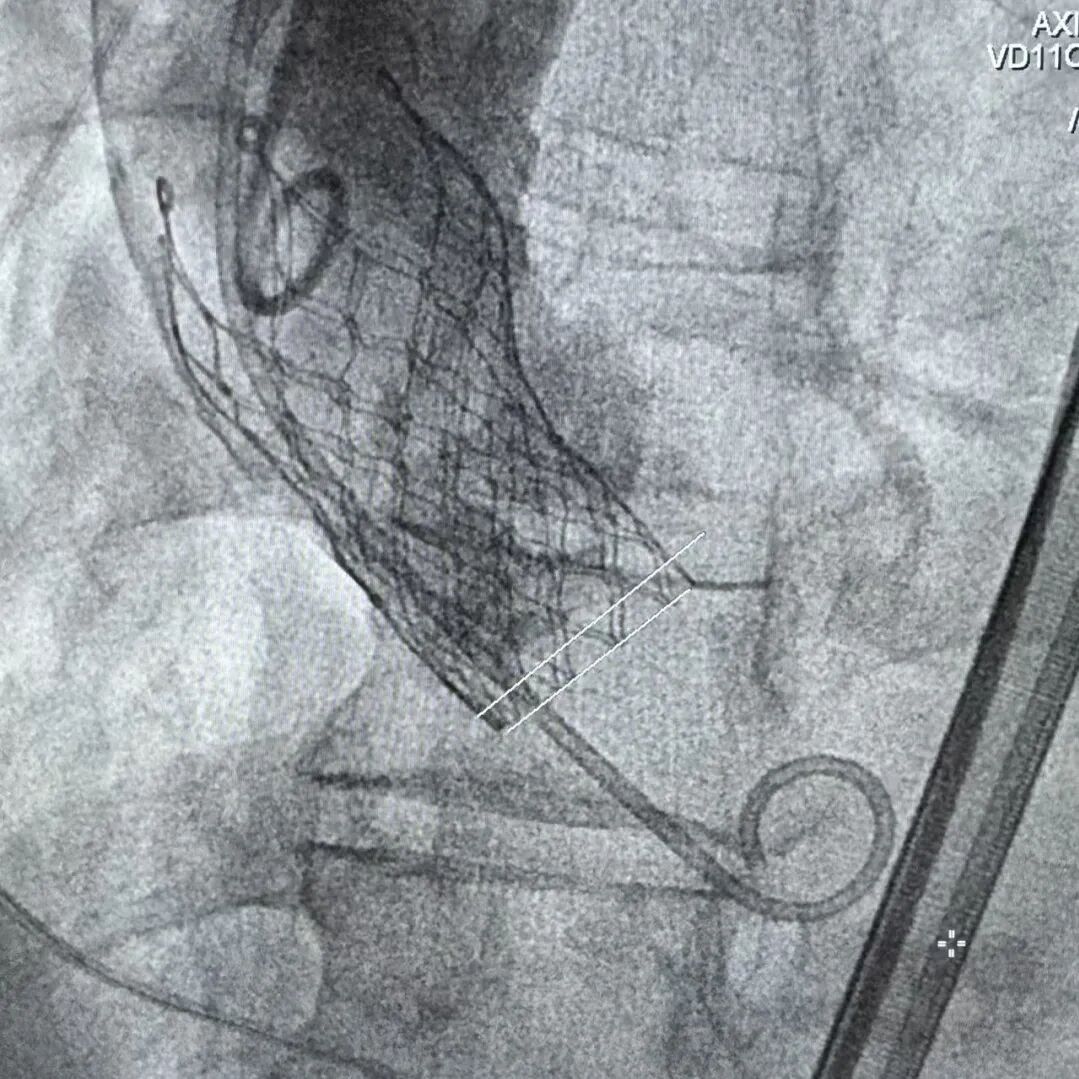

Step 4.输送系统进入:过弓性能优异,悬空通过,整体过程未将鞘管顶起至弓顶部

Step 5.瓣膜定位与释放:高起始位逐渐向下推送保持良好同轴性,无位移

Step 6.工作位观察:真实瓣环下方2mm,位置合适,决定释放,一次完成

Step 7.瓣膜脱钩:脱钩稳定无位移

Step 8.最终造影:真实瓣环下方3mm标准位,完全同轴,轻微反流,猪尾撤出后反流完全消失

Step 10.验证器械同轴性,完全同轴

瓷化升主动脉和复杂弓形一直是TAVR手术中的痛点病例,既往对于这类病例一般使用可调弯的TAVR系统辅助,此次手术使用通过性良好的自展瓣+可调弯鞘,既能满足小瓣环患者的血流动力学需求,也能大幅减小患者的手术风险。该病例既能看到Prostyle A这款预装干瓣表现了良好的通过性,在瓷化血管里推进时没有明显阻力,不用过度用力,推送十分顺畅,完全悬空通过,器械释放也很稳定;也可以看到可调弯鞘对手术过程的辅助作用,实际上对术者来说我们过往的重点都放在主要的耗材本身,辅助的耗材是否搭配起来好用,对手术的帮助也非常重要,这次手术最终还有一个亮点就是瓣膜放下去同轴性非常好,几乎是和真实瓣环平齐,这也是搭配起来产生的优秀结果。